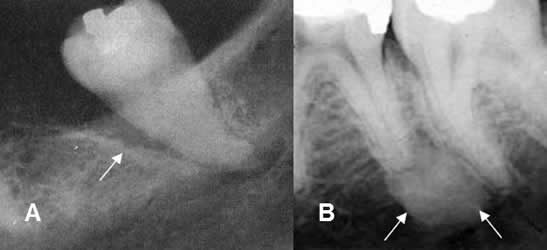

Fig 41. Enfermedad periododontal.

A y B: Rx periapical. Incremento del espacio periodontal, con lucencia que rodea las

raíces dentales y corresponde a bolsa periodontal.